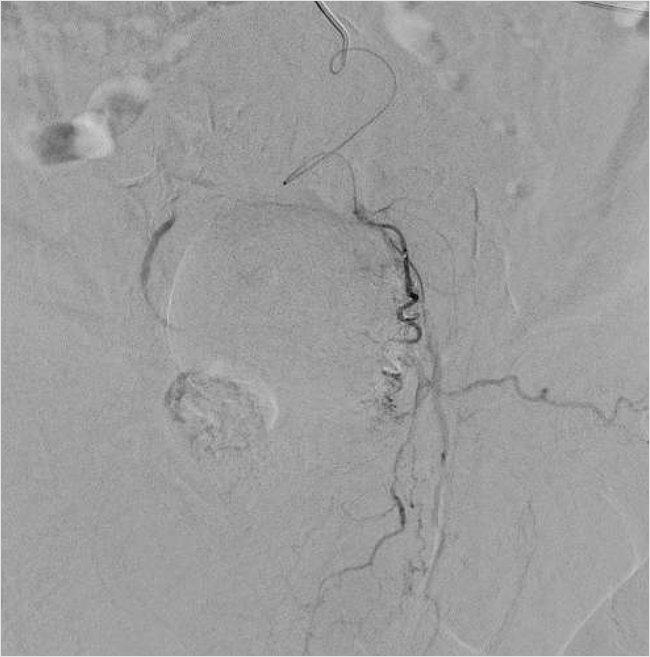

Рисунок 5. Ангиография простатической артерии справа после эмболизации

Затем была выполнена успешная окклюзия артерий с использованием микросфер (размером 100–300 мкм) до полного стаза контраста в дистальных сегментах простатических артерий (рис. 6). Дополнительных источников кровоснабжения простаты не было выявлено. Время вмешательства составило 75 мин. Доза лучевой нагрузки при проведении вмешательства составила 871 mGy. Объем введенного контрастного препарата равнялся 150 мл.